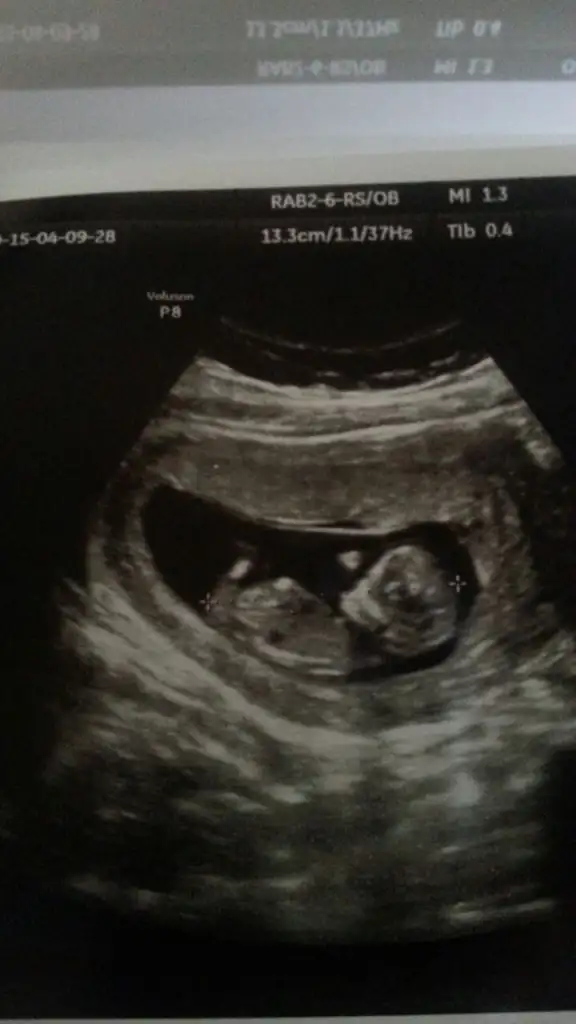

Kızlar ben de koysam yorum yapabilir misiniz. .Allah nasip ederse İkizlerim olacak.biri kız ama diğeri göstermedi kendini..Haftaya 16. Hafta dolacak o zaman gideceğim ama çok merak ediyorum..